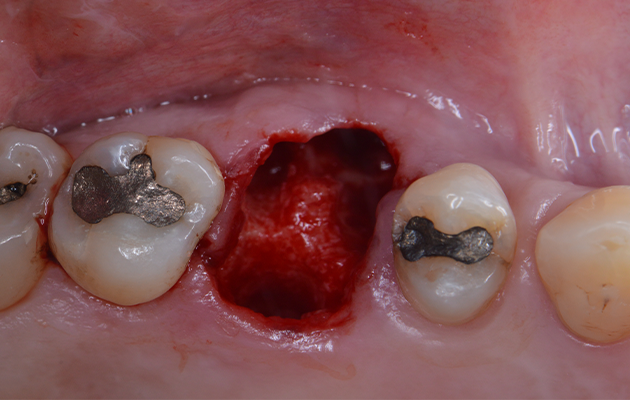

Após uma profilaxia, a paciente foi submetida à intervenção cirúrgica, foi realizada a antissepsia extrabucal e intrabucal. A região do primeiro molar superior direito foi anestesia pela técnica infiltrativa local. Após o rompimento das fibras gengivais, o dente 16 foi gentilmente removido sem a elevação de retalhos cirúrgicos com o auxílio de um fórceps, mantendo-se o septo interradicular intacto. A limpeza do leito foi realizada por meio de curetagem alveolar e copiosa irrigação com solução salina

4 | Vista oclusal mostrando o septo ósseo interradicular preservado após a exodontia